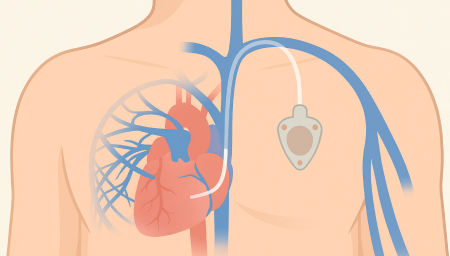

Chemoport는 항암제처럼 자극이 강한 약물을 안전하고 안정적으로 투여하기 위해 흉부 피부 아래에 이식하는 중심정맥 사용 포트입니다. 팔 혈관이 약하거나 반복 주사로 인한 통증이 걱정되는 환자에게 도움을 줄 수 있으며, 장기간 치료가 필요한 경우 편안하게 항암 치료를 지속할 수 있도록 설계되어 있습니다.

항암관(Chemoport)삽입 장점

Chemoport는 피부 아래에 완전히 이식되는 구조라 반복적인 바늘 찌름을 줄일 수 있고, 장기간 안정적인 항암제 투여가 가능합니다.또한 샤워 시에도 물이 닿지 않아도 되고, 외관 노출이 적어 일상생활에서 불편감이 비교적 적습니다.